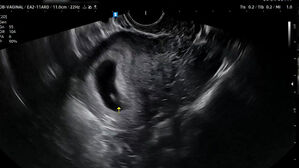

[사건X파일] 멀쩡한 태아 "긁어내라" 오진…아기 잃을 뻔한 부부 'SBS <뉴스헌터스>'를 정확히 밝혀주시기 바랍니다. ■ <뉴스헌터스> ■ 진행 : 김종원, 윤태진 앵커&… SBS 2026.01.15 19:54